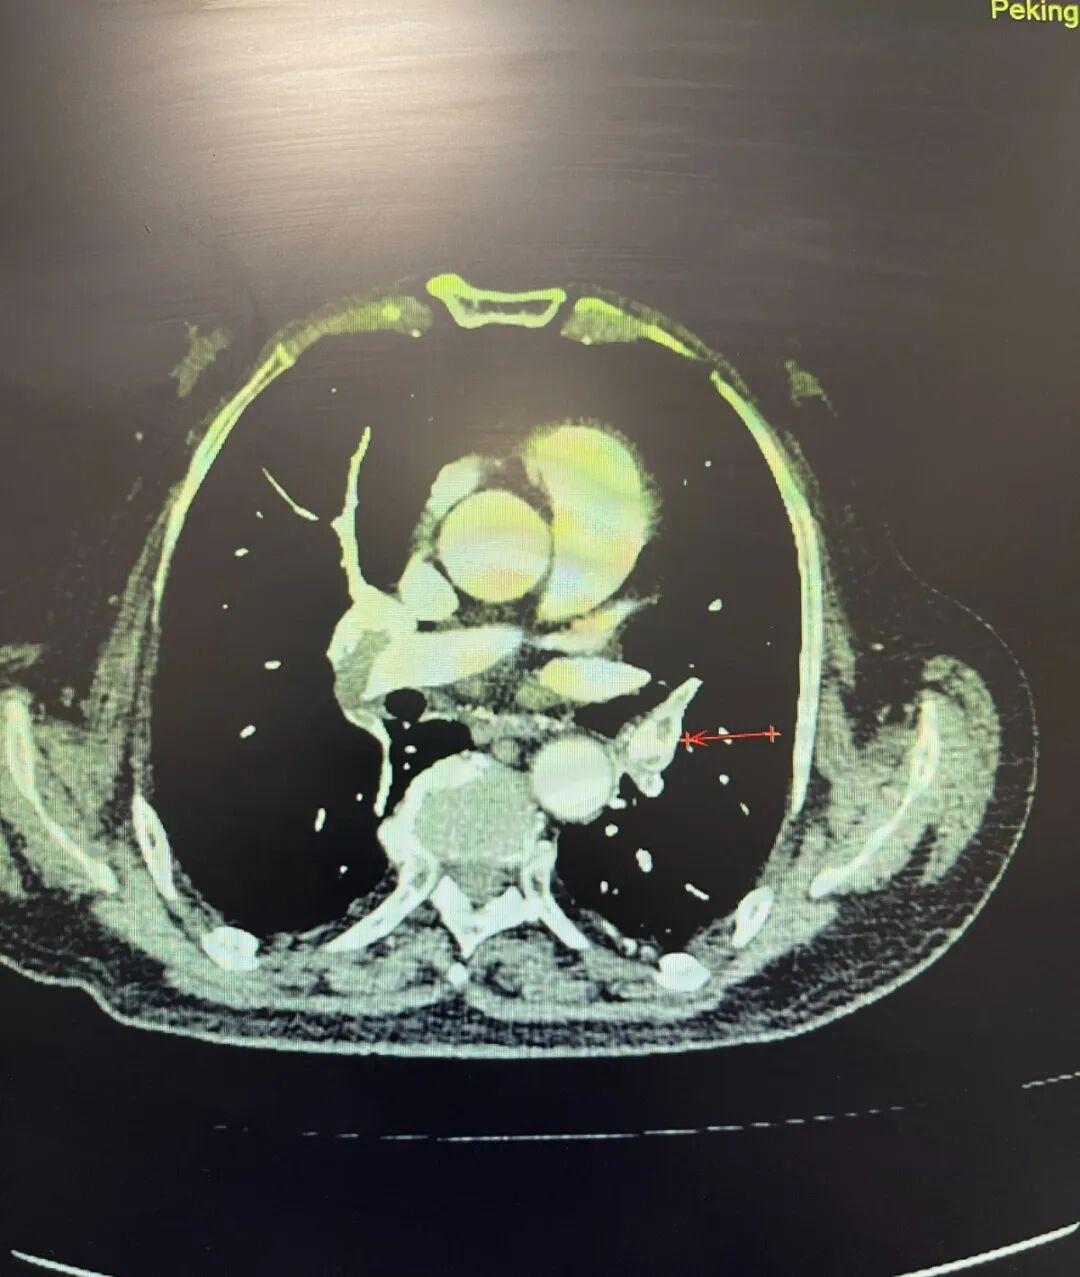

肺动脉CT血管成像清晰地显示,患者双肺动脉主干及几乎所有主要分支,都被大量血栓堵塞。